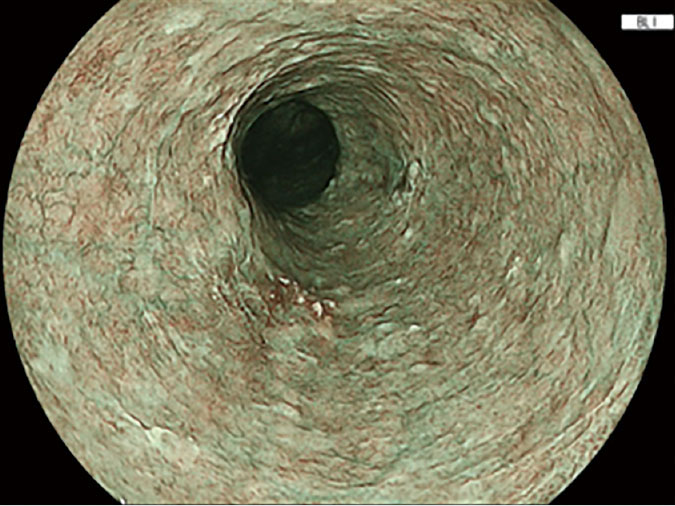

当院で使用しているFUJIFILM内視鏡では、NBIと同様に病変を見つけやすくする技術としてBLI、LCIという観察モードを使用しています。

BLI(Blue Laser Imaging)とはBLIは、特殊な青い光を使って血管や粘膜の表面構造を強調して観察する方法です。

これにより、通常の観察ではわかりにくい

などを見つけやすくなります。NBIと同じように、血管や粘膜の微細な変化を強調して観察するモードと考えていただくとわかりやすいです。